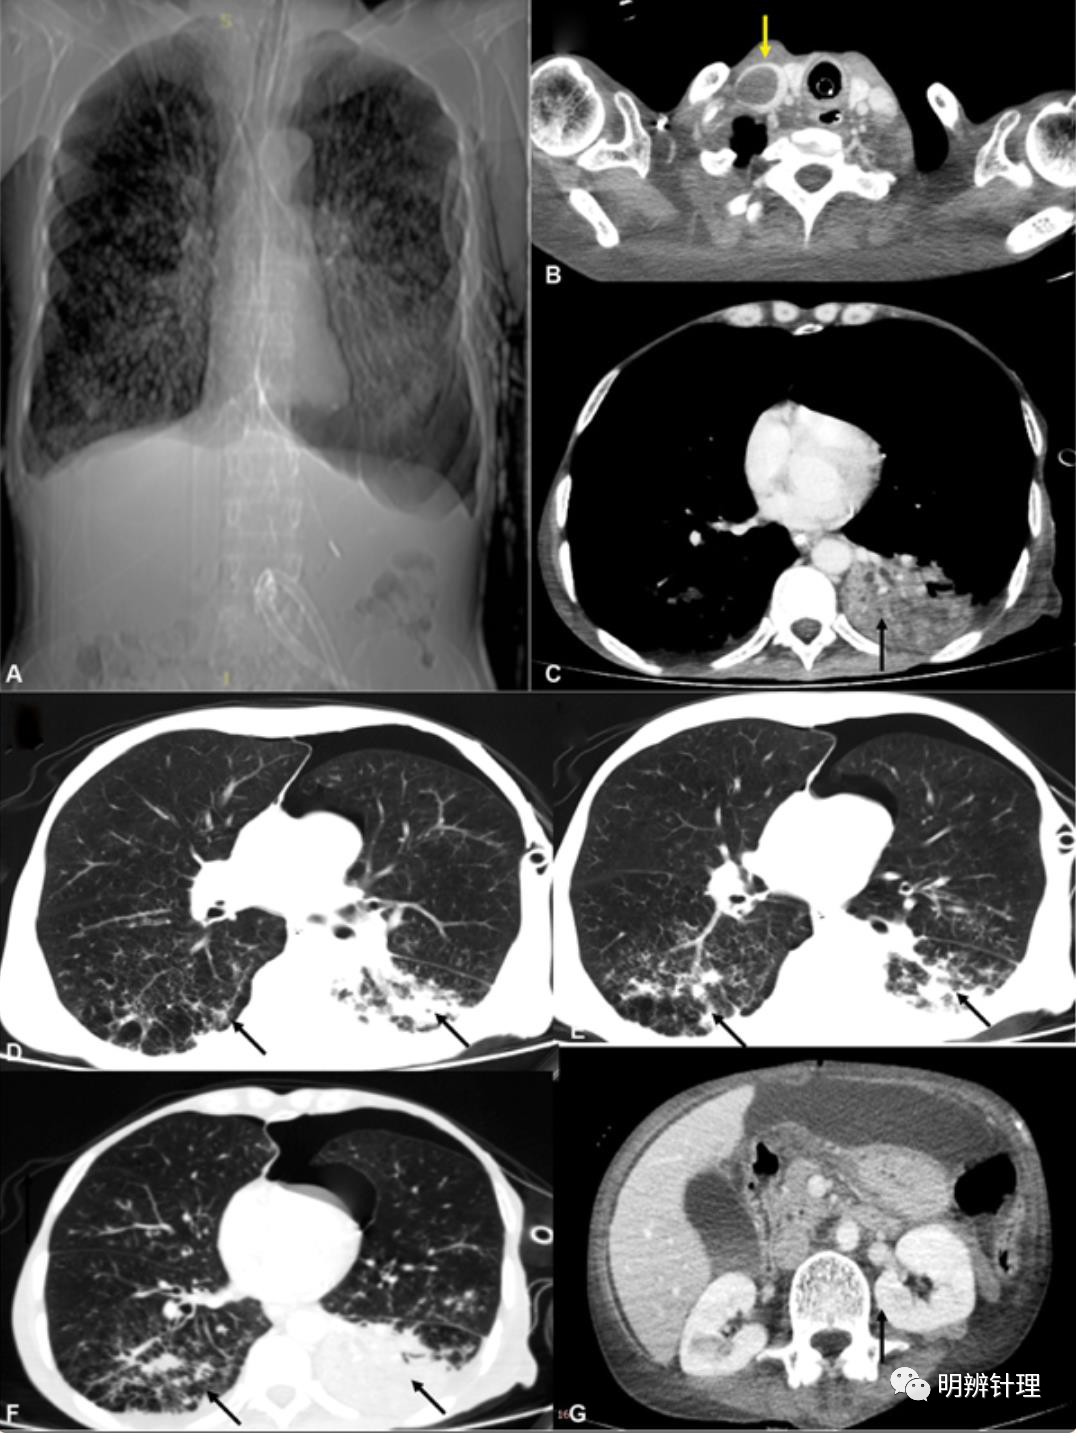

男性,60岁,长期接受哮喘类固醇治疗。最近进行了十二指肠穿孔手术,随后出现呼吸窘迫。CT显示慢性阻塞性肺病,双侧下叶浸润。增强CT ( B ) 显示右侧颈内静脉(黄色箭头)和左侧下叶实变(黑色箭头)( C ) 中的血栓。肺窗 ( D–F ) 显示双侧下叶混浊(黑色箭头),确认误吸。上腹部显示并存脓腹 ( G ),多灶性感染和败血症。

诊断结果:

血培养 葡萄球菌

链球菌 克雷伯菌